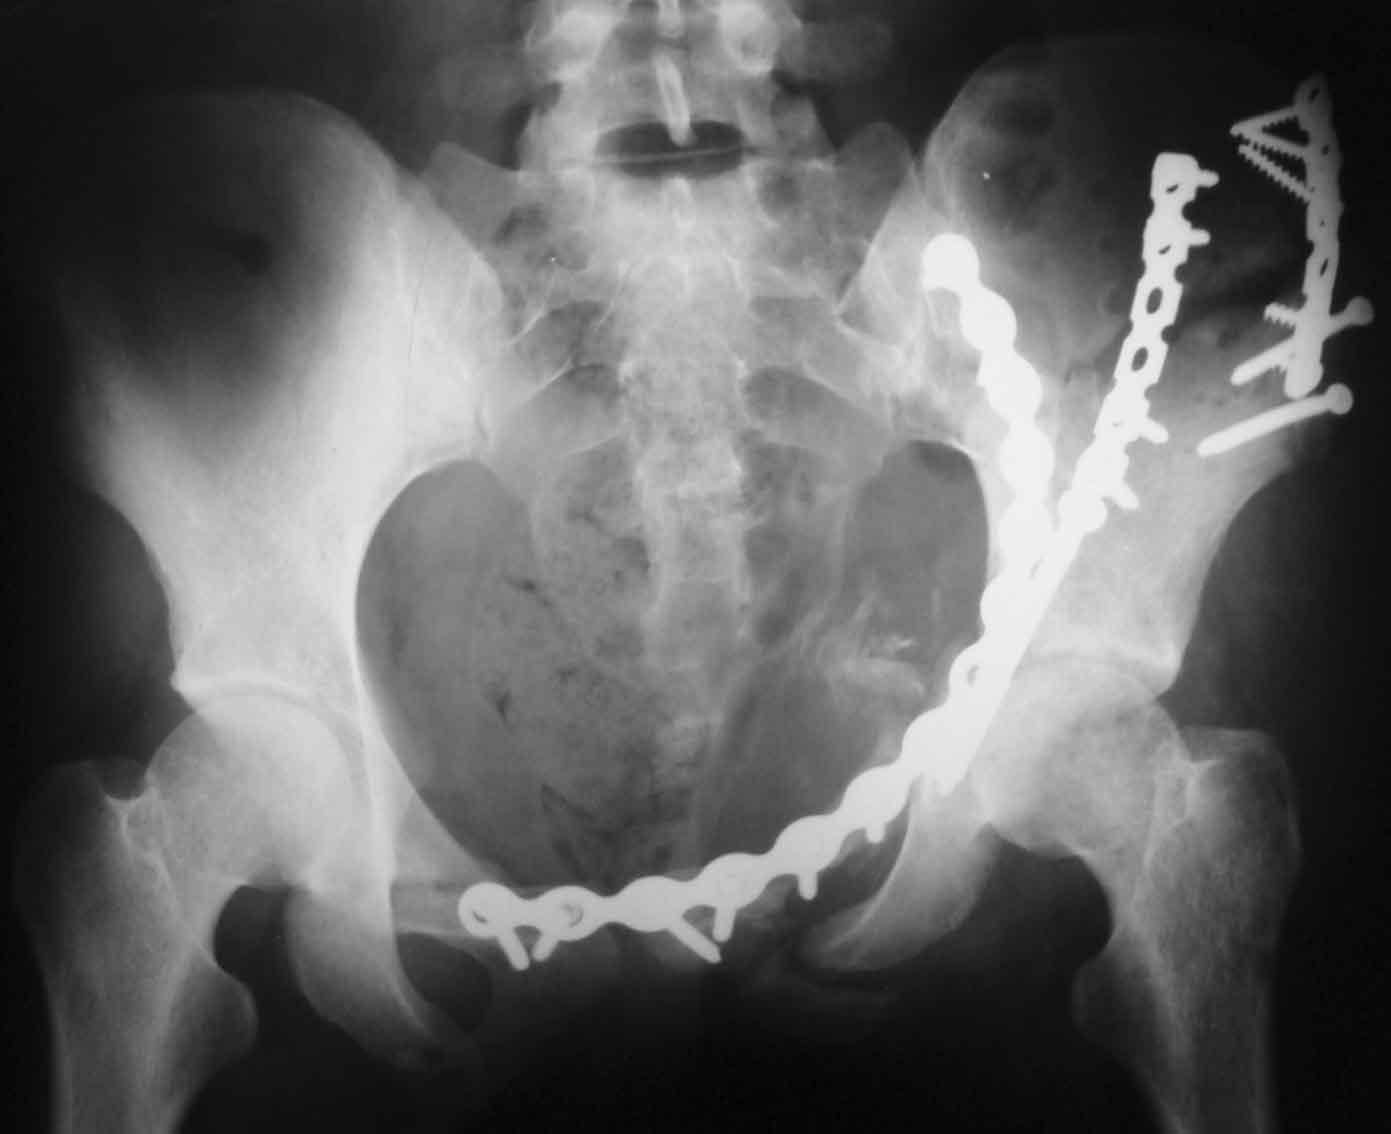

Рентгенограммы после операции

Прямая проекция

inlet

подвздошная

запирательная

A>РО - картина не очень, есть видимость винтов во впадине

По всей видимости, вы имеете в виду канюлированный винт, который проецируется на вертлужной впадине. Та вот, он проведен не через лонную, а седалищную кость. Вертлужная впадина абсолютно интактна. Это хорошо видно на проекции inlet.